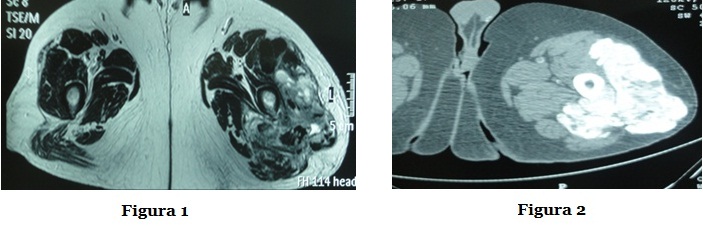

Paciente de 46 años de sexo masculino, con obesidad e IRC de causa desconocida que inicia DPA en 2007 con un cambio de icodextrina diurno. Los dosajes de fósforo fueron controlados con quelantes y los niveles de PTHi oscilaron entre 650 y 185 pg/ml (Tabla 1) en paciente con categoría IRC 5D. En 4/2012 presenta disartria, confusión y debilidad braquial derecha. En una RNM se evidencia isquemia cerebral secundaria a ACV tromboembólico. Se realiza un ecocardiograma transesofágico que diagnostica vegetación en aurícula izquierda. Inicia antibioterapia empírica con hemocultivos seriados negativos. Se efectúa reemplazo valvular mitral, con extracción de masa auricular calcificada con cultivo negativo. En 12/2012  presenta fiebre, dolor articular de cadera e induración de partes blandas en muslo izquierdo. Se realizan HC que fueron negativos e inicia tratamiento ATB. En RNM le constatan una masa heterogénea de contornos lobulados con áreas de calcificación en el tercio superior del muslo izquierdo, que se extiende hasta la región glútea, de 18 x 14 cm (Figura 1 y 2), descartándose colección. Se realizó una biopsia de la formación del muslo que muestra calcinosis pseudotumoral. Los cultivos fueron negativos para bacterias comunes, atípicas, micobacterias y hongos. Se realiza resección quirúrgica de la masa tumoral y colocación de VAC. Evoluciona afebril con mejoría clínica.